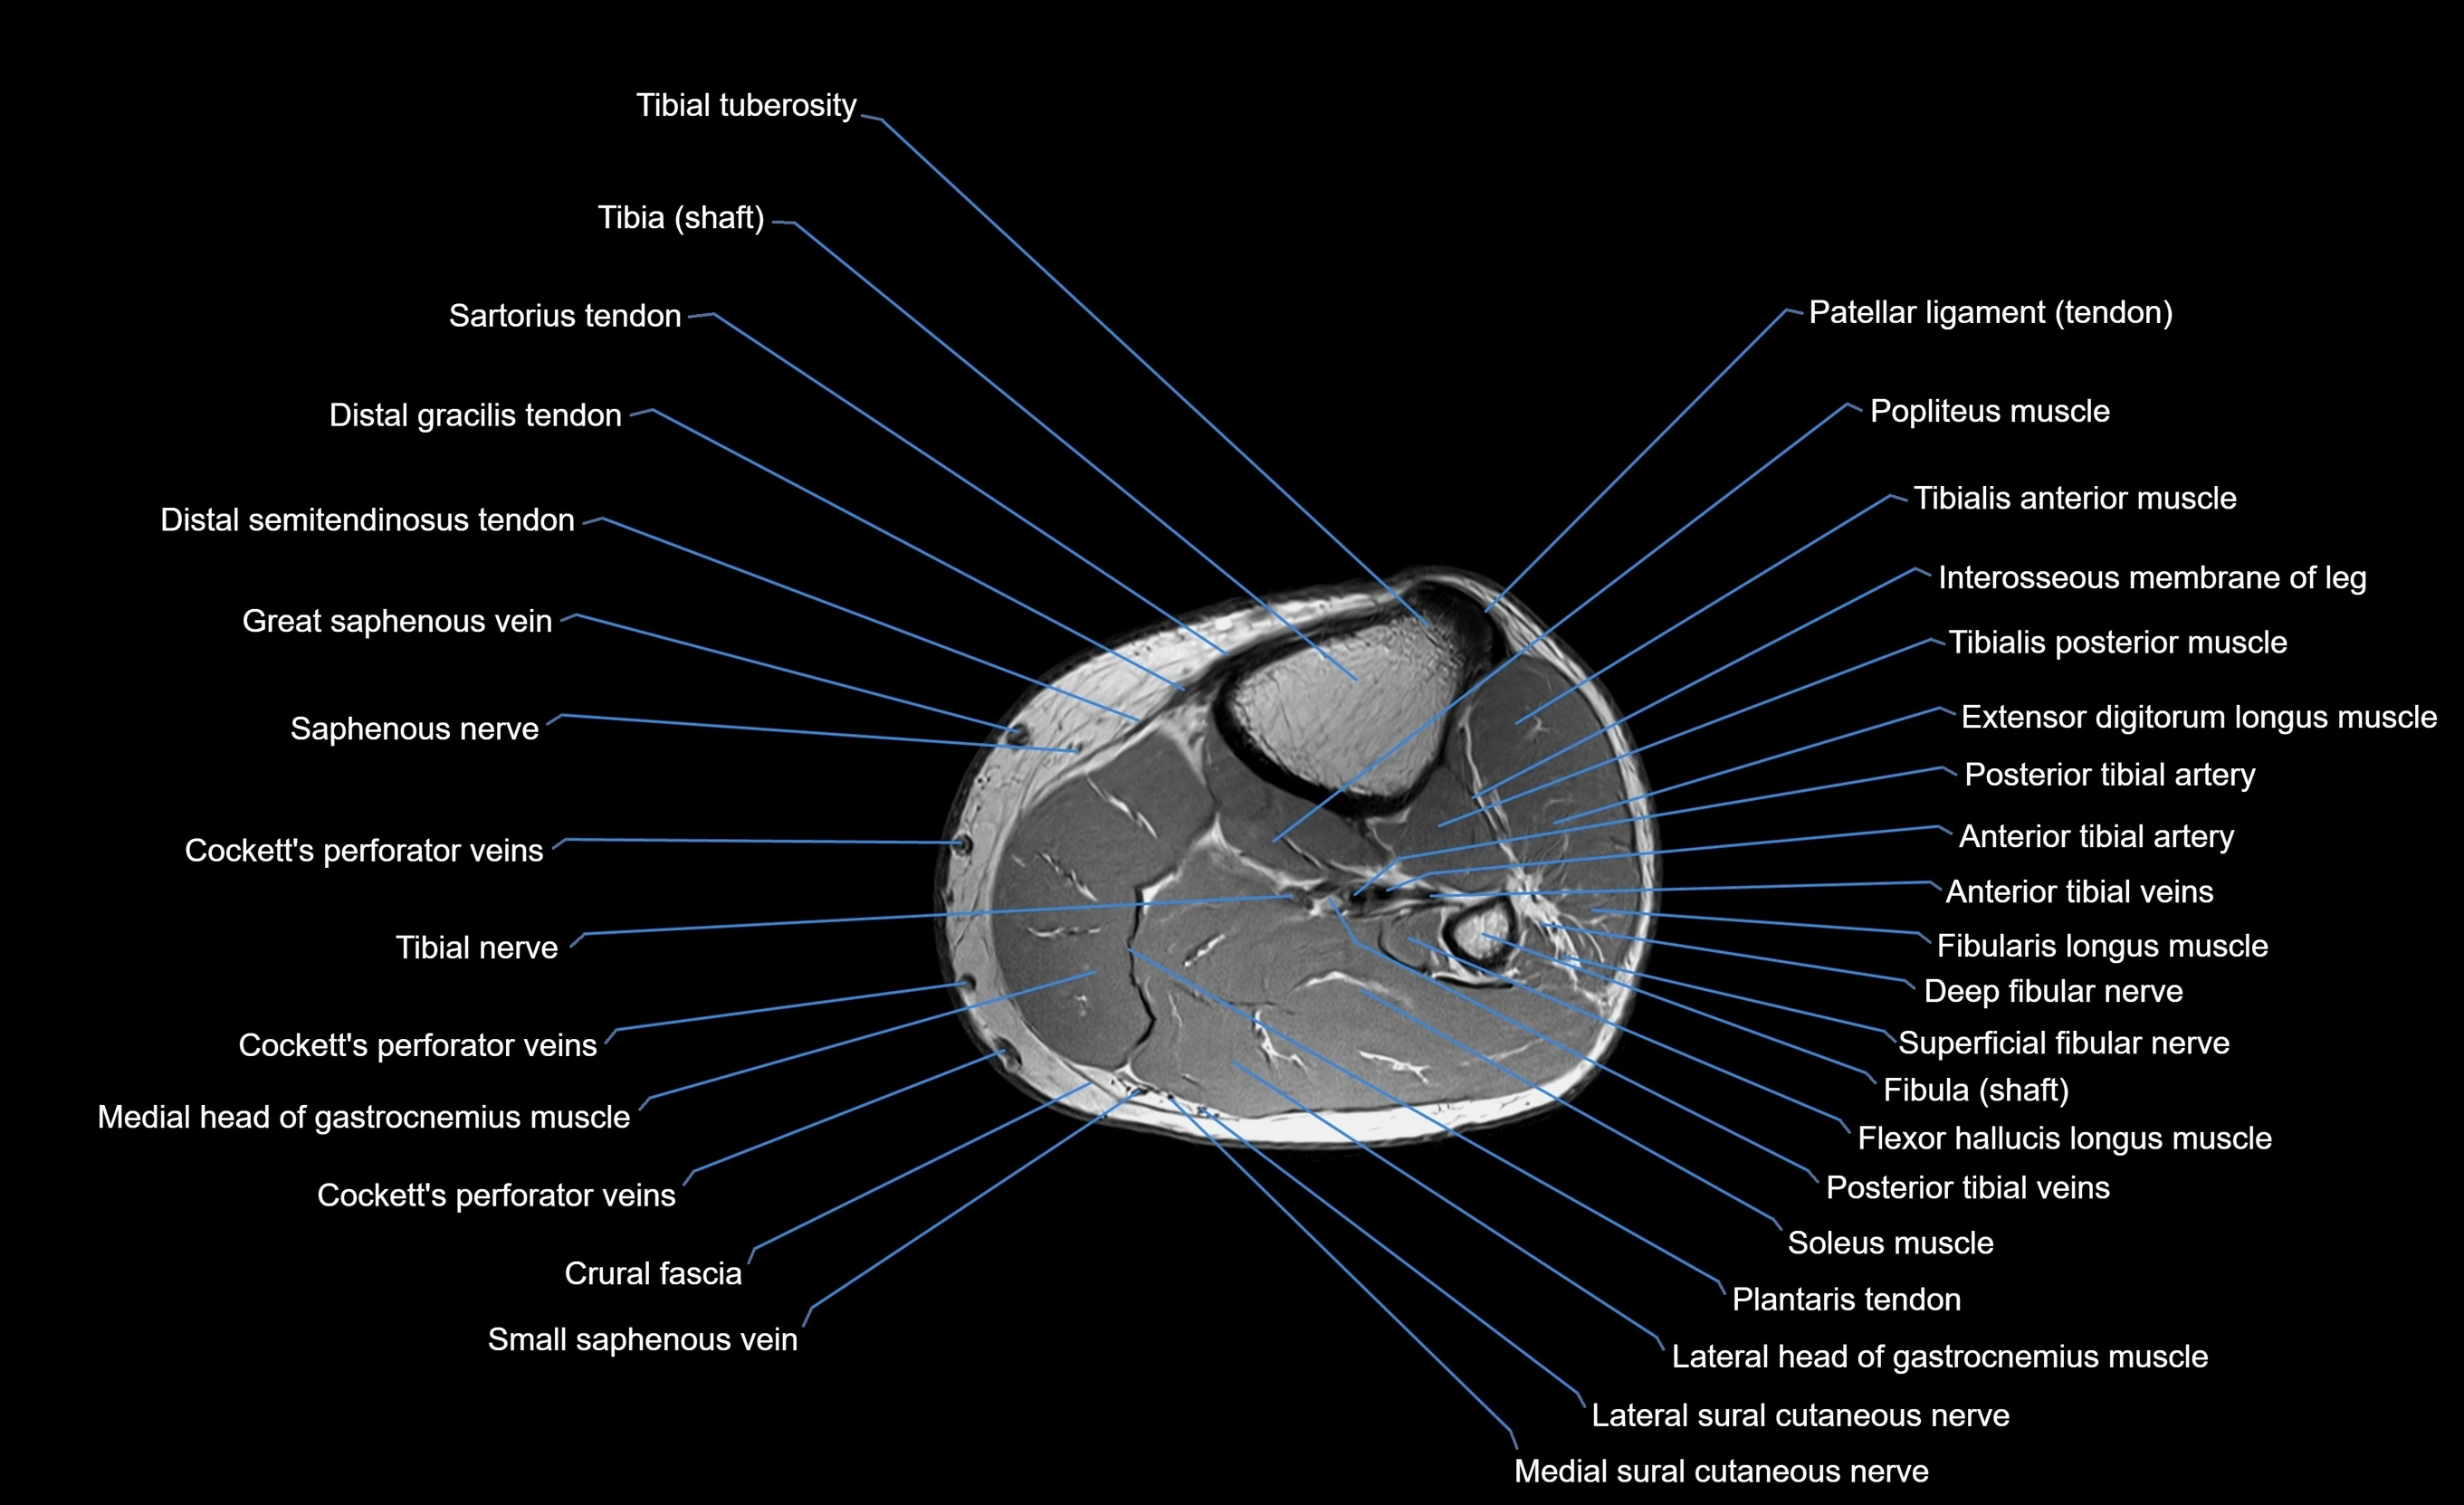

MRI image